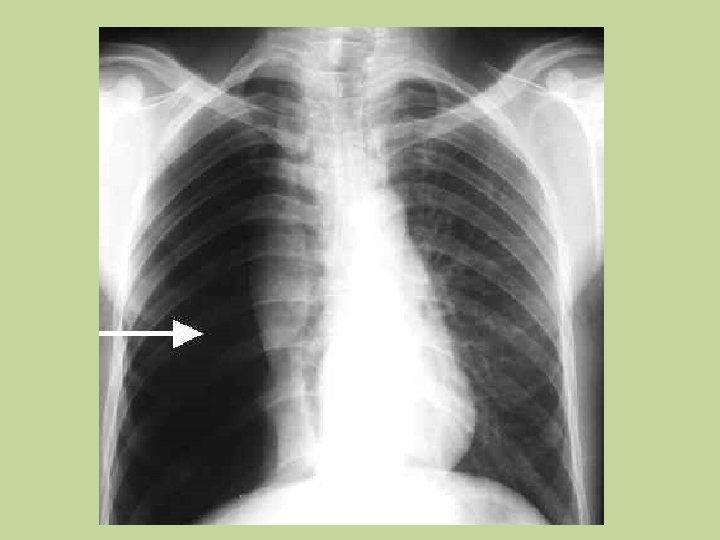

Dor Torácica P. Catastróficas VENT DEPENDENTE • Associado a dispnéia; MV abolido, e timpanismo =>(Pneumotorax) – Raio x de tórax; Analgésicos; • Associado a dispnéia, taquicardia, hemoptóicos, hipoxemia: TEP – Estratificação de Risco* – USG com Doppler MMII; ECOTT; TC helicoidal – Heparina /Trombolítico/ Tromboembolectomia.

Dor Torácica P. Catastróficas • Dor forte irradiando para dorso , região interescapular, não cede com terapêutica habitual, associada a diferença de pulsos, sinais neurológicos sopro diastólico foco aórtico = Dissecção de aorta; • RAIO-X DE TORAX: Alargamento de mediastino. • ECOTT • ECOTE • Angio Tc de Torax e Abdomen • Vasodilatadores, beta bloq; opióide, • Transferir para UTI